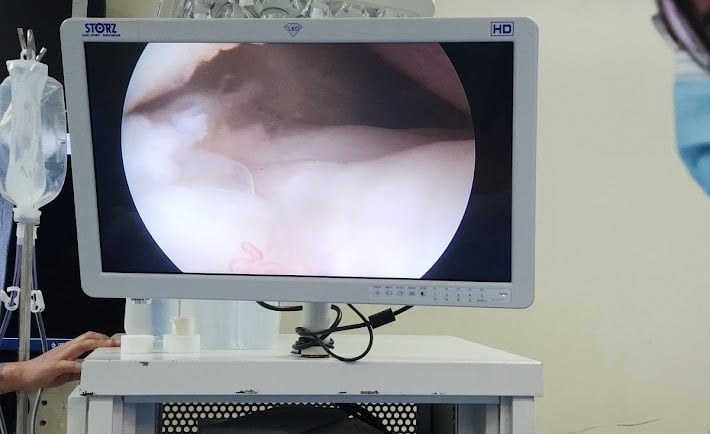

La cirugía se lleva a cabo mediante pequeñas incisiones por donde se introduce una cámara (artroscopio) y los instrumentos quirúrgicos necesarios. Esto permite al especialista visualizar directamente el interior de la rodilla y realizar reparaciones precisas sin necesidad de abrir completamente la articulación.